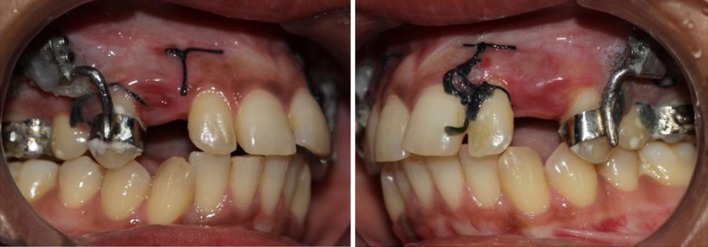

Fig. 24.

First day of distraction

Fig. 25.

Tenth day of distraction

Fig. 26.

Fifteenth day of distraction

Fig. 27.

Completed distraction in both the sides

Fig. 28.

Total distance covered measured with vernier calliper